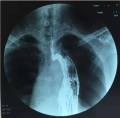

• 左上叶肺癌质子治疗后一年

肺癌是发病率和死亡率增长最快,对人群健康和生命威胁最大的恶性肿瘤之一。近50年来许多国家都报道肺癌的发病率和死亡率均明显增高,男性肺癌发病率和死亡率均占所有恶性肿瘤的第一位,女性发病率占第二位,死亡率占第二位。